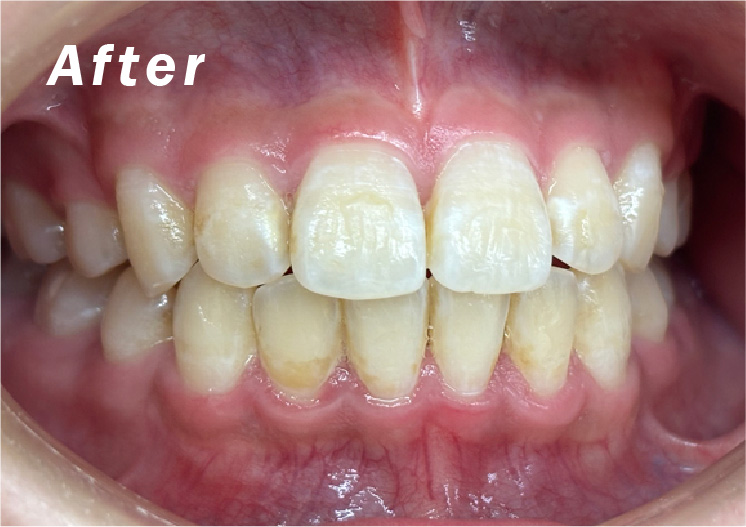

• 症例2

矯正bofore

矯正after

矯正種類 ワイヤー矯正

症例 上下額叢生

治療期間 2021年12月〜2024年10月

性別/年代 男 13歳

治療費 748,000円

治療のデメリット

• ・スペースを確保するために小臼歯の便宜抜歯が必要になる

• ・保険適用がされないので治療が高額になる

• ・後もどり、再発と再治療の可能性がある

• ・歯肉(歯ぐき)の退縮の可能性がある

• ・歯根(歯の根っこ)の吸収の可能性がある

• ・歯の失活の可能性がある

担当医師

コメント

適切な時期に治療が開始できたので、歯並びだけでなく顎や顔貌も理想的に成長しました。歯磨きもしっかりできるようになりました。